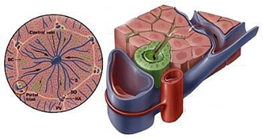

Het galwegsysteem verder uitgelegd

Het galwegsysteem bestaat uit een netwerk, of ook wel boom-achtige structuur, van galwegen in de lever en de hoofdgalweg (common bile duct, CBD) buiten de lever.

In de lever zitten smallere galwegen, vergelijkbaar met hele kleine bloedvaatjes. Zij voeren gal af vanuit de levercellen naar de steeds groter wordende galwegtakken. De rechter en linker galwegtakken in de lever verzamelen de gal en komen samen buiten de lever en vormen samen de grote galweg (CBD). Deze galweg voert de gal naar de galblaas en naar de 12-vingerige darm.

De galblaas fungeert als een reservoir voor de gal totdat eten in de 12-vingerige darm komt. Het is met een kleine galwegtak verbonden aan de hoofdgalweg, op ongeveer 1/3 van de bovenkant van de hoofdgalweg (de ductus cysticus).

Figuur 3: Het galweg systeem.

Illustratie: AMMF 2022 ©

De lever zelf bestaat uit 2 delen. Een linker helft en een rechter helft (zie figuur 4). Elk deel bestaat weer uit kleinere delen, segmenten genaamd (zie figuur 5). In totaal heeft de lever 8 segmenten. Ieder segment (deel) heeft een eigen bloedvoorziening en gal afvoersysteem (zie figuur 6).

De lever zelf bestaat uit 2 delen. Een linker helft en een rechter helft (zie figuur 4). Elk deel bestaat weer uit kleinere delen, segmenten genaamd (zie figuur 5). In totaal heeft de lever 8 segmenten. Ieder segment (deel) heeft een eigen bloedvoorziening en gal afvoersysteem (zie figuur 6).

Figuur 5: Bron NTVG

Figuur 6: Bron: John Hopkins Medical Centre